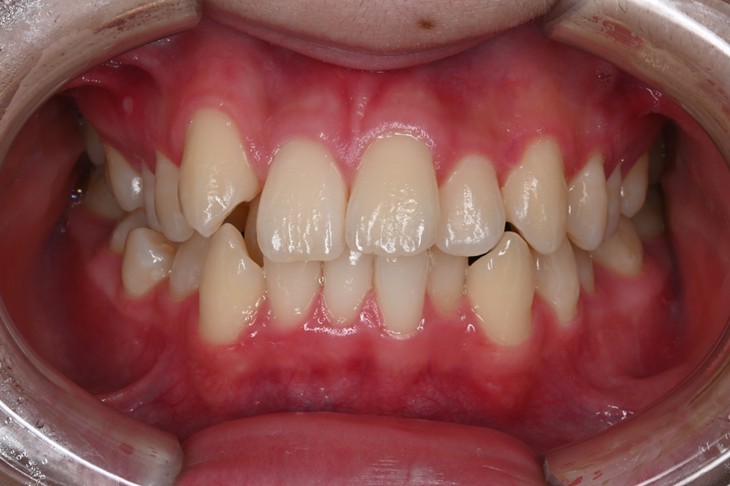

症例2:八重歯が気になる

| 患者様データ | 20代 女性 |

| 来院主訴 | 八重歯が気になる。 |

| 治療内容 | 八重歯を治すために上の親知らずを抜歯し、インビザラインにてマウスピース矯正を開始しました。かみ合わせを整えるためにゴムかけを行いました。 |

| 概算治療費 | 約85万円 |

| 治療期間 | 1年3ヶ月 |

| 通院回数 | 8回 |